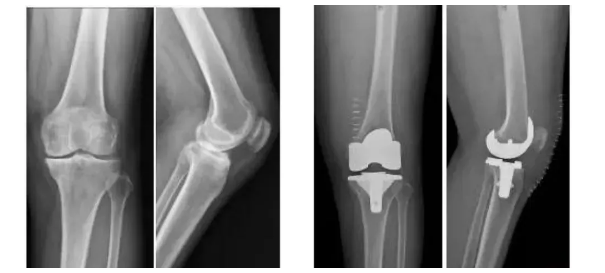

膝關(guān)節(jié)骨關(guān)節(jié)炎是一種退行性疾病,近年隨著經(jīng)濟(jì)發(fā)展和人口老齡化趨勢日趨明顯,尤其是在中老年群體發(fā)病率較高,因此膝關(guān)節(jié)置換術(shù)需求量日益增長。此外,隨著居民生活水平的提高,大多患者對于膝關(guān)節(jié)置換術(shù)術(shù)后的生活質(zhì)量和植入假體有了更高的要求,隨之假體在設(shè)計(jì)和創(chuàng)新方面也更精準(zhǔn)、更便捷化。全球shou款3D打印分區(qū)骨小梁生物型膝關(guān)節(jié)假體正是在這種高需求與高期待的新形勢下應(yīng)運(yùn)而生。

目前臨床上使用的膝關(guān)節(jié)假體多為骨水泥固定型假體,骨水泥即骨粘固劑,它可以將膝關(guān)節(jié)假體固定在骨界面上。骨水泥固定存在一定局限,如骨水泥單體具有一定的毒性;與骨接觸面的骨溶解問題;隨著時間推移,會發(fā)生變形和退變等。

本次植入的生物型膝關(guān)節(jié)假體在術(shù)中無需使用骨水泥,通過機(jī)械方式進(jìn)行固定,即假體與骨組織的緊密結(jié)合,獲得假體的初始穩(wěn)定性,遠(yuǎn)期骨組織長入假體表面的微孔內(nèi)部,實(shí)現(xiàn)由機(jī)械固定向生物.內(nèi)鎖固定的轉(zhuǎn)化,zui終經(jīng)過骨整合作用獲得良好固定,預(yù)期能夠獲得更長的假體壽命。此外,生物型膝關(guān)節(jié)假體避兔了骨水泥相關(guān)并發(fā)癥的發(fā)生,縮短了手術(shù)時間,zui大程度保留了骨組織。因而減輕了患者術(shù)后疼痛,降低了圍術(shù)期并發(fā)癥發(fā)生率,有利于患者術(shù)后快速康復(fù)。

周宗科教授介紹說,該款3D打印分區(qū)骨小梁生物型膝關(guān)節(jié)假體有三個亮點(diǎn),一是脛骨平臺假體采用了3D打印骨小梁分區(qū)技術(shù),三分區(qū)設(shè)計(jì)使宿主骨均勻骨長入,避免因應(yīng)力分布不均而造成平臺假體松動等問題;二是所用股骨髁假體表面為真空等離子噴涂純鈦涂層,其粗糙的接觸面增加了骨誘導(dǎo)的能力,具有優(yōu)異的即刻穩(wěn)定和長期穩(wěn)定性;三是所用平臺墊為添加維生素E的高交聯(lián)超高分子量聚乙烯材質(zhì),具有優(yōu)異的耐磨性能。